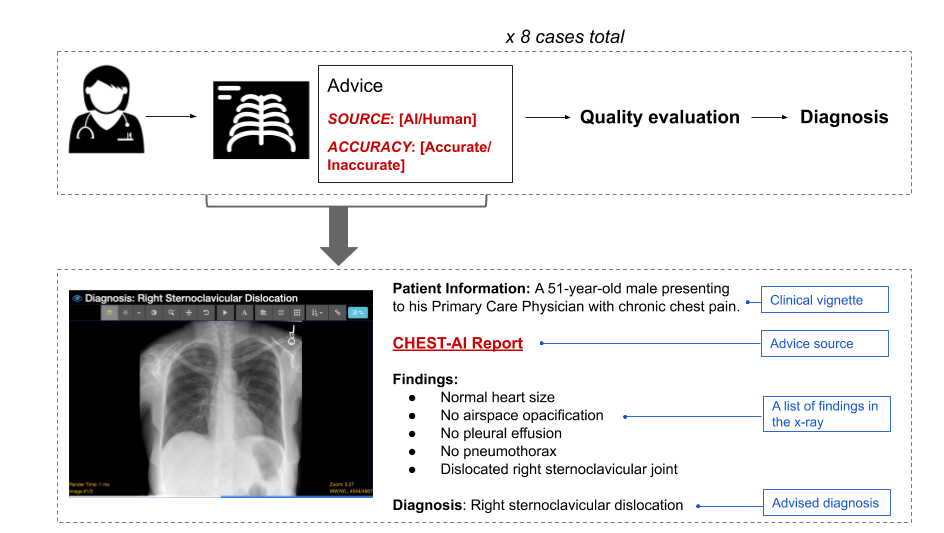

Our paper focuses on how expert and non-expert physicians modulate their trust in AI-generated advice in order to walk a tight line: if physicians do not trust AI advice they will not use it, but blind trust could lead to medical errors. To evaluate this dynamic, we presented radiologists and internal/emergency medicine (IM/EM) physicians with a series of chest x-rays and diagnostic advice. We varied two things: whether we presented the advice as coming from an AI system or a fellow radiologist, and whether the advice was correct or incorrect.